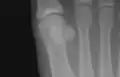

The first metatarsal. (Left.)